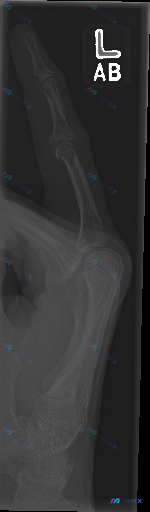

整理到一份左手第一掌指关节区域的侧位X光影像资料,先放出来和大家讨论一下。 影像报告里明确说: - 骨皮质连续,未见透亮骨折线、脱位或半脱位 - 关节间隙正常,无骨质破坏或骨膜反应 - 未见明显软组织肿胀或异物影 - 综合结论是「骨骼结构未见明显外伤性/炎症性/肿瘤性病变迹象」 但影像分析里也特别提...